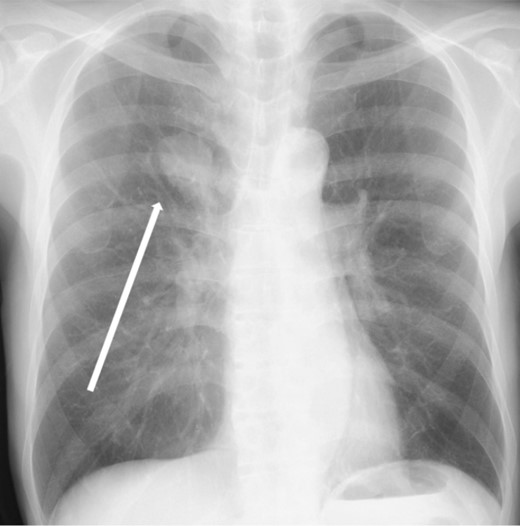

The patient was a 73-year-old man. He had a history of arteriosclerosis obliterans in the lower extremities, transient atrial fibrillation, and was consuming two antiplatelet agents. The patient had a fever within the range of 38°C. Blood tests showed an elevated white blood cell (WBC) count of 31.6 × 103/μl (neutrophil, 90.2%), CRP of 9.67 mg/dl, and APTT of 125.4 s. Chest radiography revealed an abnormal shadow in the upper lobe of the right lung (Fig. 1). Contrast-enhanced chest CT revealed an irregularly shaped mass, 43 × 33 × 28 mm in size, in the upper lobe of the right lung (Fig. 2). 18F-fluorodeoxyglucose-positron emission tomography showed abnormal accumulation with a maximum standardized uptake value of 28.4 in a pointed lesion in the upper lobe of the right lung (Fig. 3). A bronchoscopic biopsy was performed, and the patient was diagnosed with non-small cell carcinoma.

Chest X-ray findings (frontal view). Mass shadow in the upper lobe of the right lung.